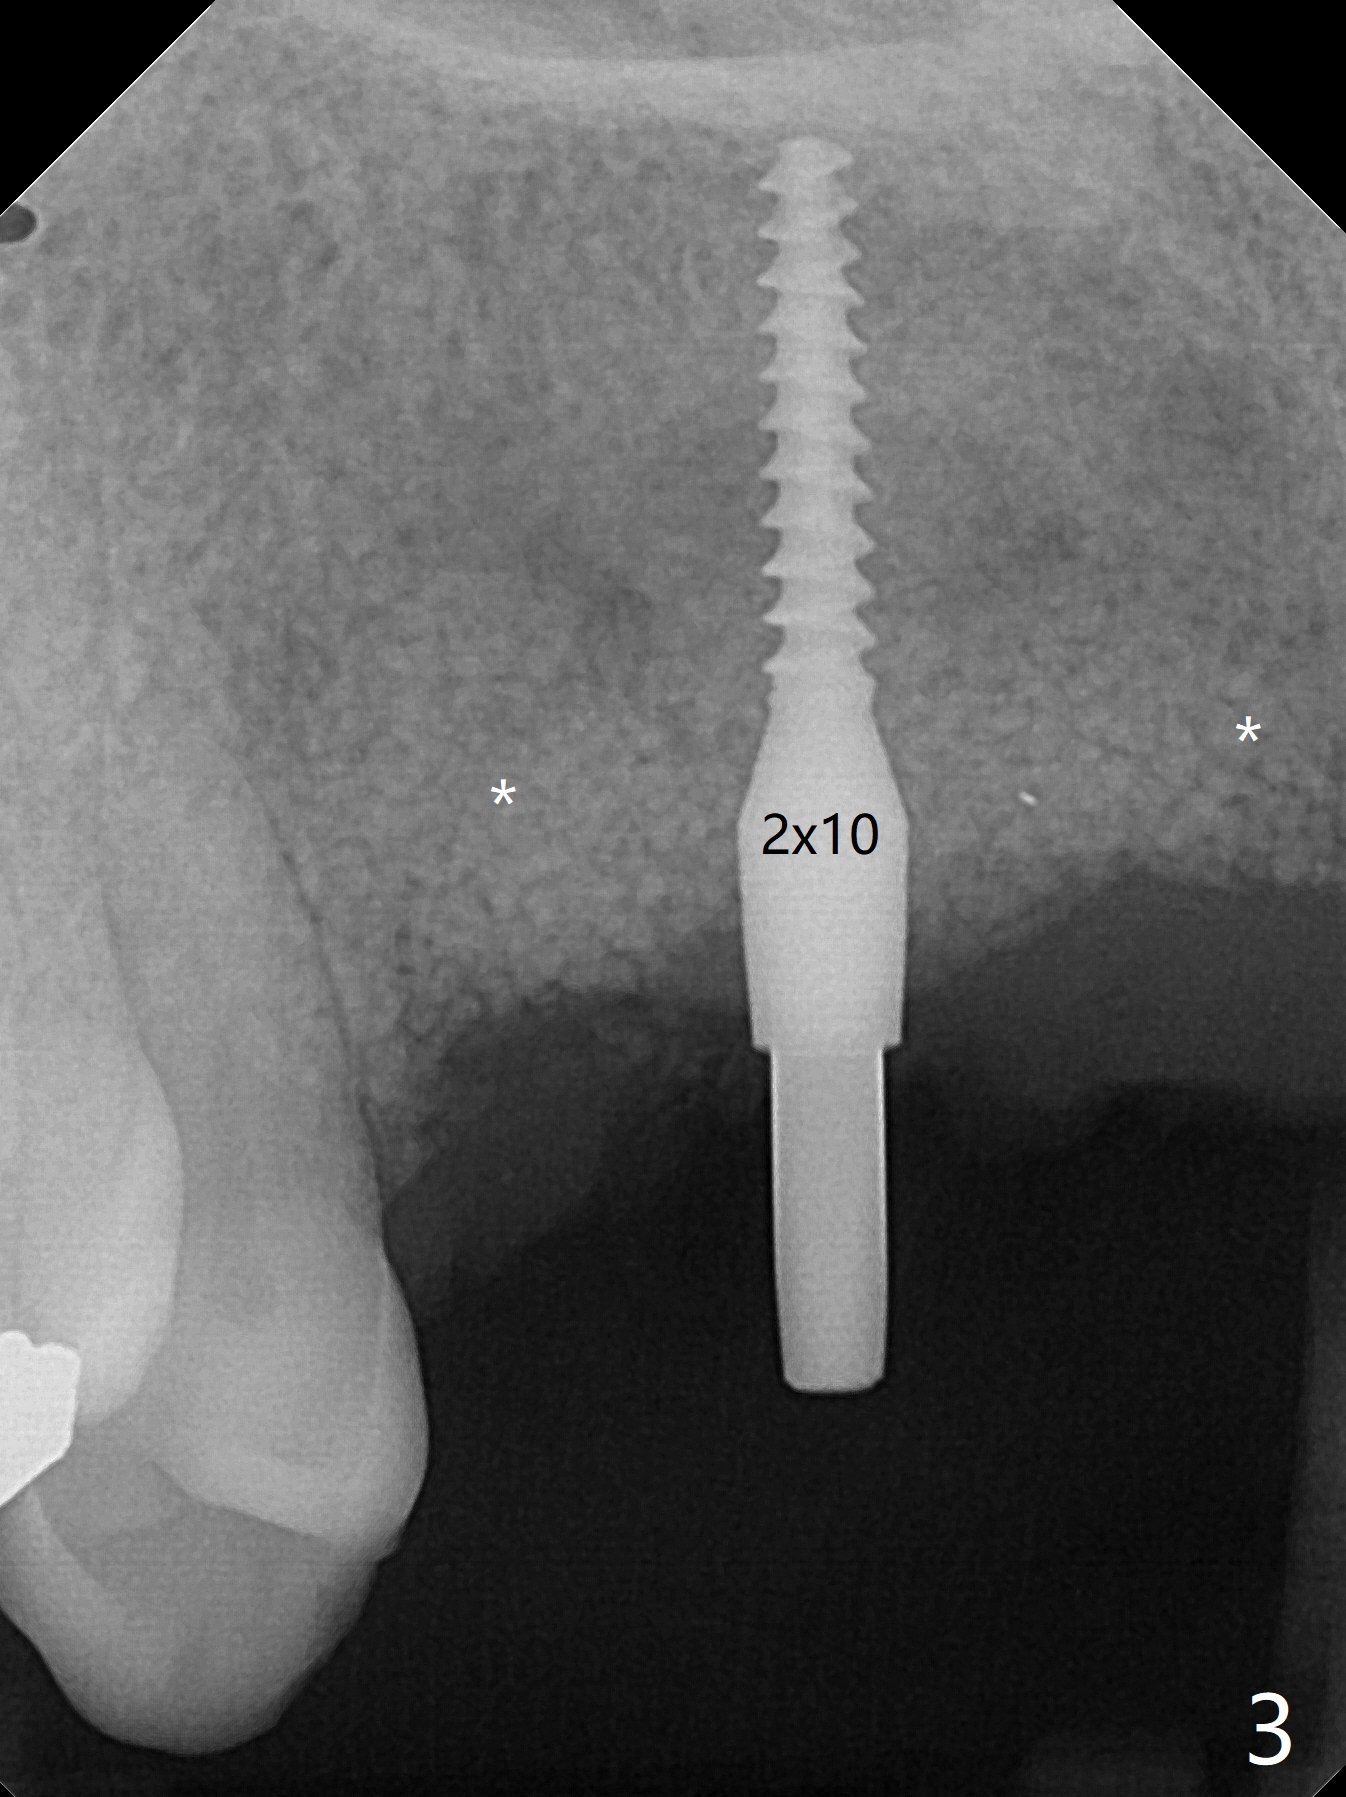

5,7号牙两段式植体种植后螺纹暴露,植骨后4-5个月,准备5号牙uncover,病人主诉7号牙出血,切开后发现两个植体螺纹仍旧暴露(图一,二),看样子保留不住,而6号牙位牙槽嵴不宽,准备植入2x8.5毫米一段式植体,结果骨质高度允许植入10毫米植体(图二,三),然后使用外科钻头和环形刀(trephine bur)取出两段式植体,填入粘性骨粉(图三:*),覆盖PRF和不可吸收膜,4-0 PGA缝合(图四),最后牙周敷料。5,7牙位愈合也可以植入一段式植体,让植体之间距离大些,植骨后颊侧腭侧宽度也可能不足。